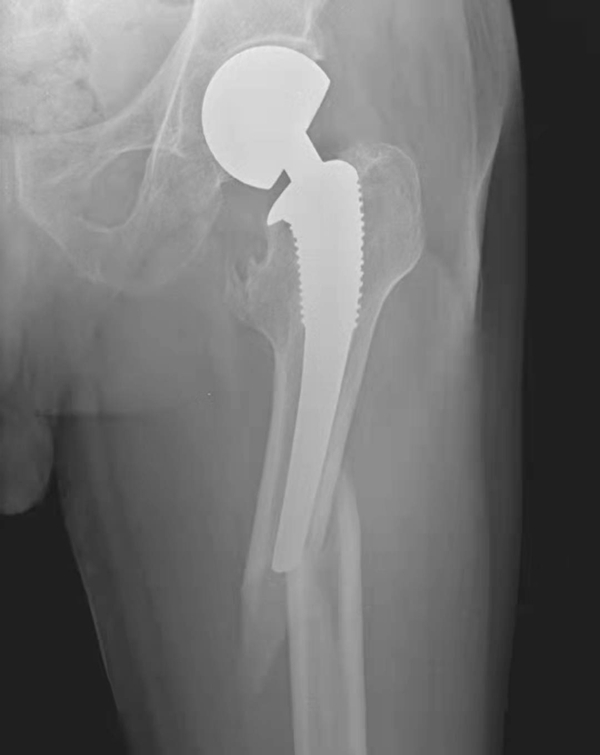

图12 假体磨损

X线片,示左侧人工股骨柄近端外侧可见假体磨损碎屑(黑箭),同时柄部周围骨质吸收溶解